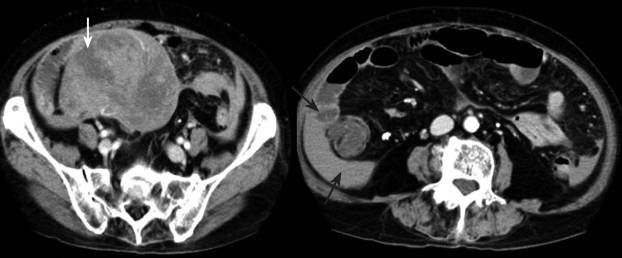

- Chụp CT, MRI, PET

Trong đó, siêu âm nội soi và sinh thiết vừa giúp chẩn đoán chính xác, vừa phân loại giai đoạn khối u.